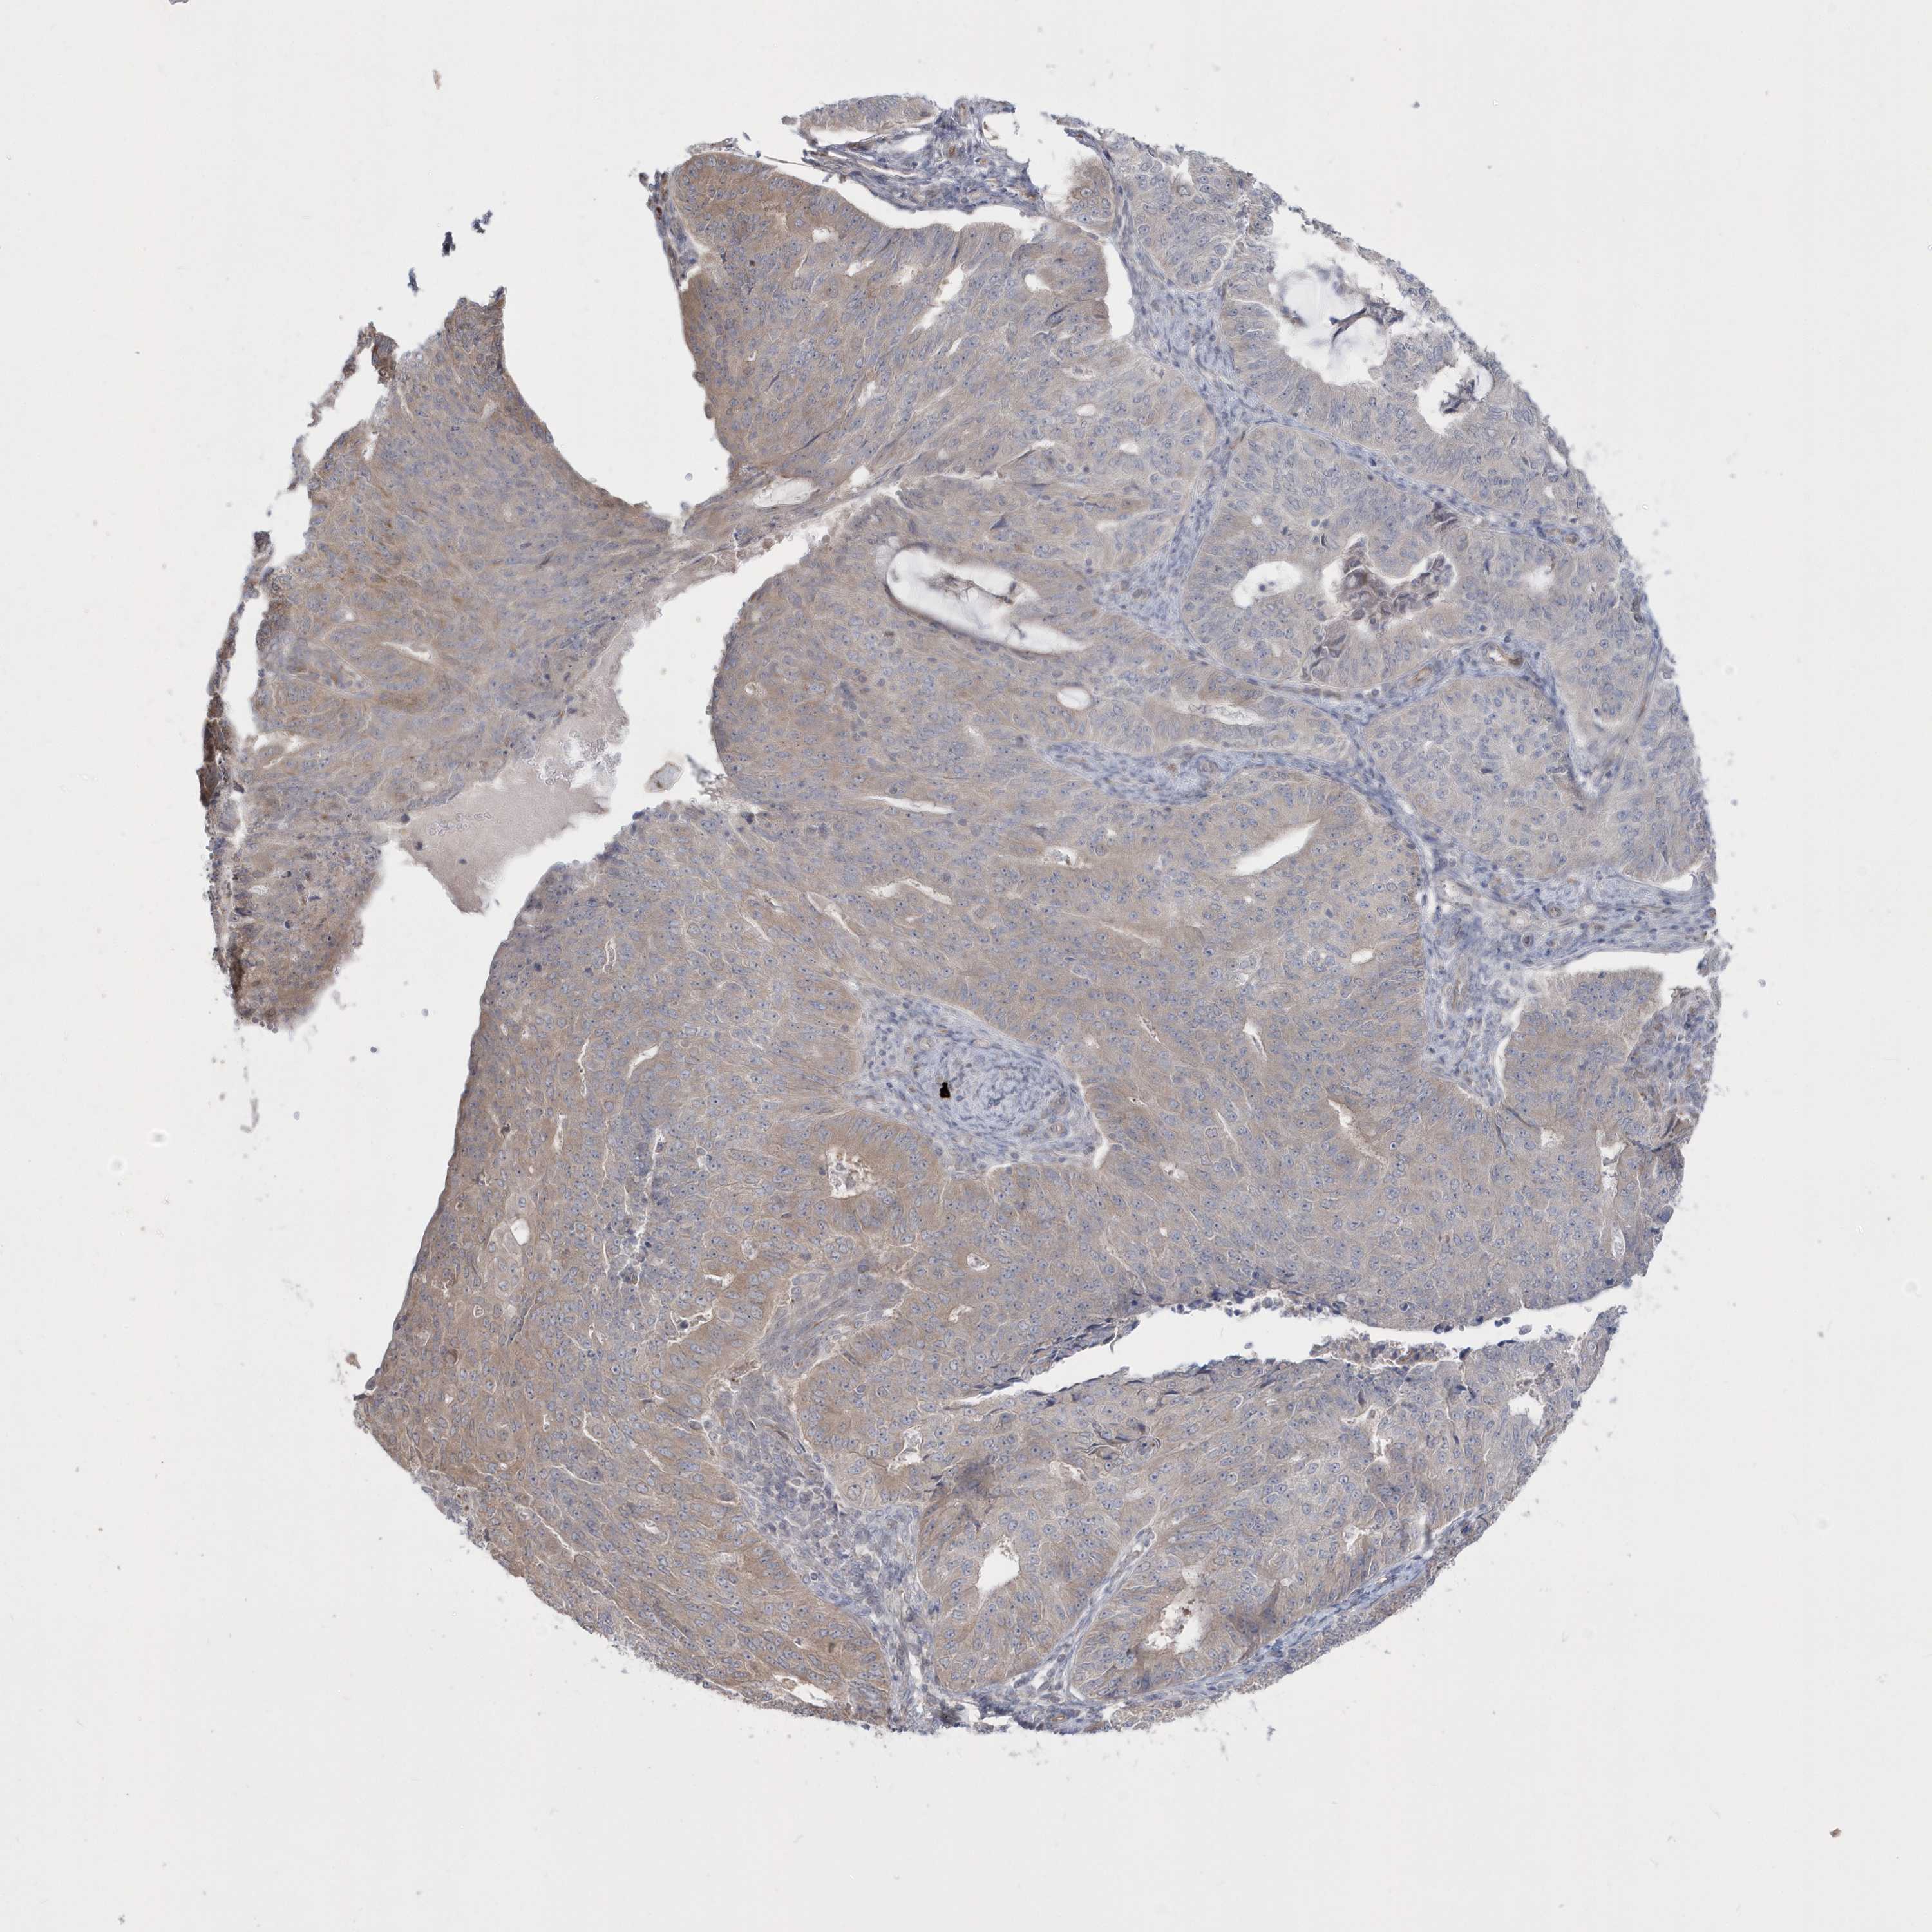

ENDOMETRIAL CANCER - Protein expressioni

A mouse-over function shows sample information and annotation data. Click on an image to view it in a full screen mode. Samples can be filtered based on level of antibody staining by selecting one or several of the following categories: high, medium, low and not detected. The assay and annotation is described here.

Note that samples used for immunohistochemistry by the Human Protein Atlas do not correspond to samples in the TCGA dataset.

Antibody stainingi

Antibody staining in the annotated cell types in the current human tissue is reported as not detected, low, medium, or high, based on conventional immunohistochemistry profiling in selected tissues. This score is based on the combination of the staining intensity and fraction of stained cells.

Each image is clickable and will lead to virtual microscopy that enables deeper exploration of all samples and also displays staining intensity scores, fraction scores and subcellular localization as well as patient and tissue information for each sample.

Antibody HPA036160

Staining

High

Medium

Low

Not detected

Intensity

Strong

Moderate

Weak

Negative

Quantity

>75%

75%-25%

<25%

None

Location

Nuclear

Cytoplasmic/membranous

Cytoplasmic/membranous,nuclear

Adenocarcinoma, NOS